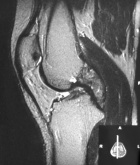

26 year old female with pain and swelling in the right knee for two years

Zoom image: Radiological image Radiological image.